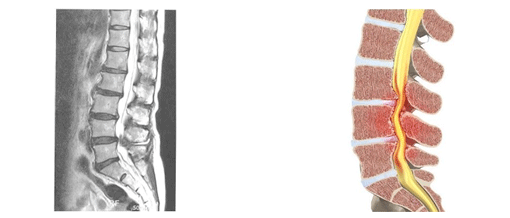

ôÃß°ü ÇùÂøÁõ

ô¼ö ½Å°æÀÌ Áö³ª°¡´Â ôÃß°üÀÌ º¯¼º°ú ³ëÈ·Î ÀÎÇÏ¿© ³»°æÀÌ Á¼¾ÆÁö¸é¼ ½Å°æµéÀÌ ´·Á »ý±â´Â ÁúȯÀÔ´Ï´Ù. ¼±ÃµÀûÀ¸·Î Á¼Àº ºÐµéµµ ÀÖÁö¸¸ ´ë°ÔÀÇ °æ¿ì ô¼ö½Å°æÀÌ Áö³ª°¡´Â Åë·Î(ôÃß°ü)°¡ ³ªÀ̰¡ µé¸é¼ ôÃß°üÀ» µÑ·¯½Ñ ôÃß»À ¸¶µð°¡ ±½¾îÁö°Å³ª ÁÖÀ§Àδ밡 µÎ²¨¿öÁ® ôÃß°üÀÌ Á¼¾ÆÁö´Â ÅðÇàÇö»óÀÌ ¹ß»ýÇÕ´Ï´Ù.

ôÃß°üÇùÂøÁõÀº µð½ºÅ© Å»ÃâÁõó·³ ½Å°æÀÌ ´·Á ´Ù¸®°¡ Àú¸° Áõ»óµîÀÌ ³ªÅ¸³ªÁö¸¸ µð½ºÅ©º´°ú´Â ±¸º°µÇ´Â Áõ»óÀÌ ³ªÅ¸³ª¸ç µð½ºÅ©º´Àº Áö¼ÓÀûÀÎ ÇÏÁö ÅëÁõÀ» È£¼ÒÇÏ´Â ¹Ý¸é ôÃß°üÇùÂøÁõÀÇ °æ¿ì ¼Àְųª °ÉÀ» ¶§ ÅëÁõÀÌ À¯¹ßÀÌ µË´Ï´Ù. ¶ÇÇÑ Ã´Ãß°ü ÀÚü°¡ Á¼¾ÆÁ® ½Å°æ´Ù¹ßÀ» ÀüüÀûÀ¸·Î ´©¸£´Â °ÍÀ̱⠶§¹®¿¡ ¾ûµ¢ÀÌ, °ñ¹Ý ºÎÀ§¿Í ´Ù¸®Àüü°¡ ¾ÆÇÁ°í, Á¾¾Æ¸® ºÎÀ§¿¡ Áã°¡ Àß ³ª´Â °ÍÀÌ Æ¯Â¡ÀÔ´Ï´Ù.

ôÃß À¯ÇÕ¼ú / ±â±â °íÁ¤¼ú

ôÃß°íÁ¤¼úÀº ôÃßÀÇ ¿Ü»óÀ̳ª ÅðÇ༺ º¯¼º, ¼ö¼ú ÈÄ ÈÄÀ¯Áõ, Á¾¾ç, ¿°Áõ, ¼±Ãµ¼º ±âÇü µî ôÃßÀÇ ±¸Á¶Àû ÀÌ»óÀ» Àç°ÇÇÏ´Â ¼ö¼ú¹ýÀÔ´Ï´Ù. 8~10cm Á¤µµÀÇ Àý°³¸¦ ÇÊ¿ä·Î Çϸç, Àΰøµð½ºÅ©³ª ³ª»ç¸øÀ» »ç¿ëÇØ ôÃߺÐÀýÀÌ Èçµé·Á ¹Ì²ô·¯Áö´Â °ÍÀ» ¸·°í, °íÁ¤µÈ ºÎÀ§°¡ ¸ö¹«°Ô¸¦ ÃÖ´ë·Î ¹ÞÃÄ ¾ÈÁ¤µÇ°Ô ÇØÁÝ´Ï´Ù.

µð½ºÅ© ¸¶µð¸¦ ±»È÷´Â ¼ö¼ú

- A : µ¹ÃâµÈ µð½ºÅ©¸¦ Á¦°ÅÇϸé

- B : ôÃß»À°¡ ºÒ¾ÈÀüÇØÁú ¼ö ÀÖ´Ù.

- C : À̸¦ ¿¹¹æÇϱâ À§ÇØ À§, ¾Æ·¡ ôÃß»À¸¦ ±»Çô ÁÖ´Â À¯ÇÕ¼úÀ» ½ÃÇàÇÑ´Ù.